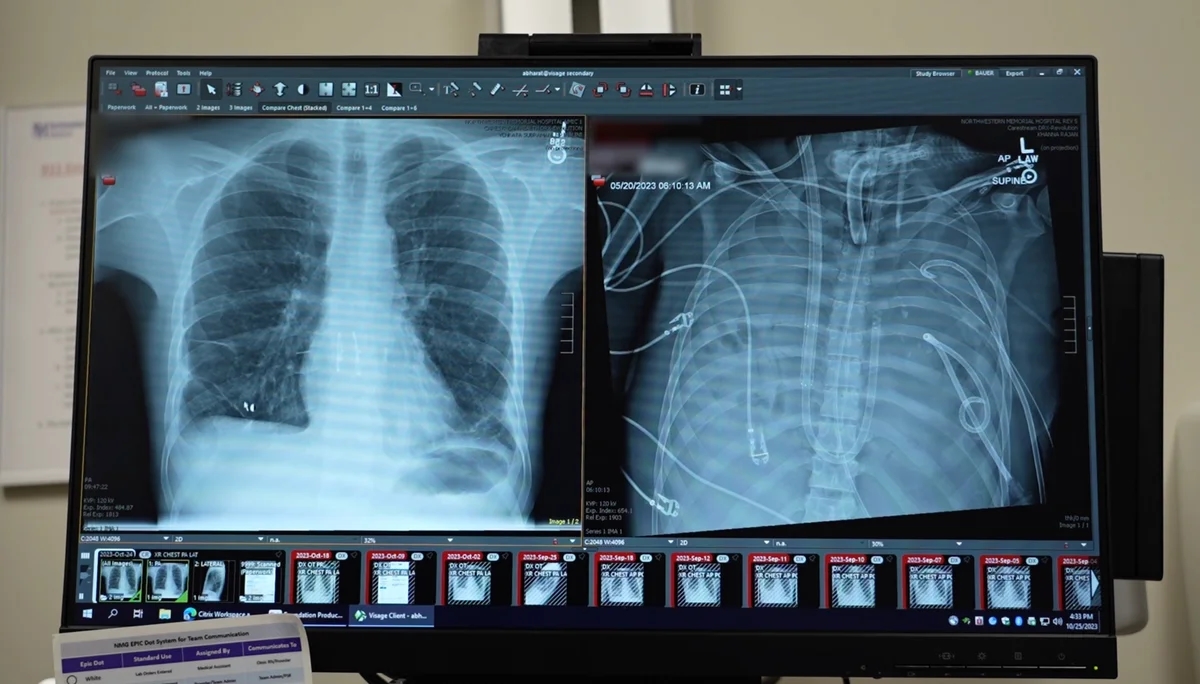

Cerrahlar, kanı vücut dışında oksijenlendiren gelişmiş bir yapay dolaşım sistemi kurdu. Bu sistem, iki gün boyunca kandaki karbondioksiti temizledi ve oksijen sağladı. Aynı zamanda kalbin üzerindeki basıncı dengeledi. Böylece diğer organların toparlanması için zaman kazanıldı.

Uygun donör akciğerler bulunduğunda hastanın genel durumu nakli kaldırabilecek seviyeye gelmişti. Operasyon başarıyla tamamlandı. Çıkarılan eski akciğerler incelendiğinde dokunun tamamen geri dönülemez şekilde hasar gördüğü doğrulandı.